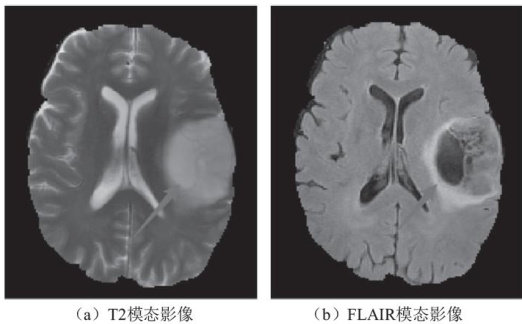

摘要:胶质瘤是中枢神经系统最常见的原发性脑肿瘤,胶质瘤的基因分型对诊断与治疗至关重要,其中异柠檬酸脱氢酶(IDH)突变状态是关键的预后标志。传统依赖术后组织样本的检测方法存在延迟,而非侵入性磁共振成像(MRI)结合深度学习为术前预测提供了新思路。文中提出一种双流融合网络(DSFNet),用于多模态MRI胶质瘤IDH基因分型。该网络通过注意力引导的非对称双路径特征提取(ADFE)模块与基因分类器,深度挖掘T2和FLAIR模态的异质性特征。ADFE模块结合卷积神经网络与注意力机制,强化局部和全局特征融合,基因分类器则通过多尺度特征实现精准分型。在BraTS2020数据集上的实验表明,DSFNet的IDH分型准确率达 92.0% ,AUC为0.90,优于现有方法,为胶质瘤的精准诊疗提供了高效的非侵入性解决方案。